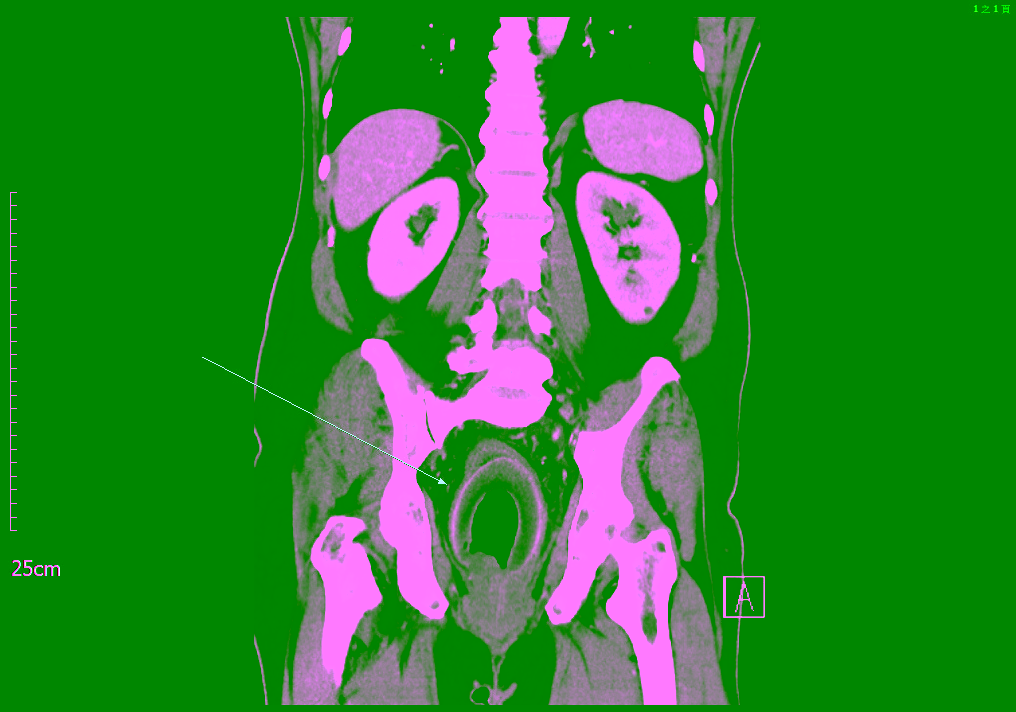

該56 歲的男性患者痛苦求醫,主訴兩天前出現嚴重腹痛,尿量減少和嚴重便秘。患者無其他發燒、噁心或嘔吐等症狀,經體格檢查,生命體徵也穩定,腹部檢查則發現腹部膨脹、壓痛,有反彈痛;再經影像學檢查,腹部電腦斷層掃描(CT)顯示,直腸內有一個巨大的空心異物,壓迫前列腺尿道,導致尿滯留,約有一兩千cc的尿液無法排出。

↑圖說:腹部電腦斷層掃描顯示直腸內有空心異物。(圖片來源:義大醫院提供)